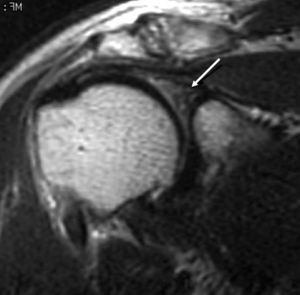

Lesiones del intervalo del manguito de los rotadores

El intervalo del MR es el espacio más o menos triangular localizado entre el borde anterior del tendón del supraespinoso y el borde superior del tendón subescapular. Este espacio anatómico está cubierto por la cápsula articular y contiene las siguientes estructuras (fig. 31): el LGHS, el LCH, el TLB y el borde anterosuperior del borde glenoideo. Los puntos de origen e inserción de estas estructuras se han descrito anteriormente, sin embargo es de notar que la relación entre el TLB y los LGHS y LCH, cambia a medida que estas tres estructuras se extienden desde sus puntos de origen hasta la zona proximal de la corredera bicipital (fig. 6). A nivel medial, aproximadamente a la altura de la articulación glenohumeral, el LCH se encuentra por encima del TLB y el LGHS se encuentra por delante de ambos. A nivel del troquiter el LGHS se coloca por delante y por debajo del TLB. A nivel de la parte proximal de la corredera bicipital, el LGHS se halla por debajo del TLB, mientras que el LCH permanece por encima del TLB. Esta distribución anatómica provee una estabilidad del TLB durante el movimiento del hombro (polea reflectora).

Fig. 31.--Intervalo de los rotadores. Artrorresonancia sagital oblicua T1 con supresión grasa, que revela el espacio entre el borde anterior del músculo supraescapular y el borde superior del músculo supraespinoso (cabezas de flecha). Dentro del espacio se encuentra, además de la cápsula, el tendón largo del bíceps (TLB), el ligamento coracohumeral (LCH) y el ligamento glenohumeral superior (LGHS).

Las lesiones del intervalo del MR pueden afectar a cualquiera de las estructuras contenidas dentro de este espacio anatómico y, en general, son producidas por un traumatismo agudo con desplazamiento de la cabeza humeral hacia delante y arriba. Así mismo, el borde superior del tendón subescapular se halla frecuentemente afectado (fig. 32).